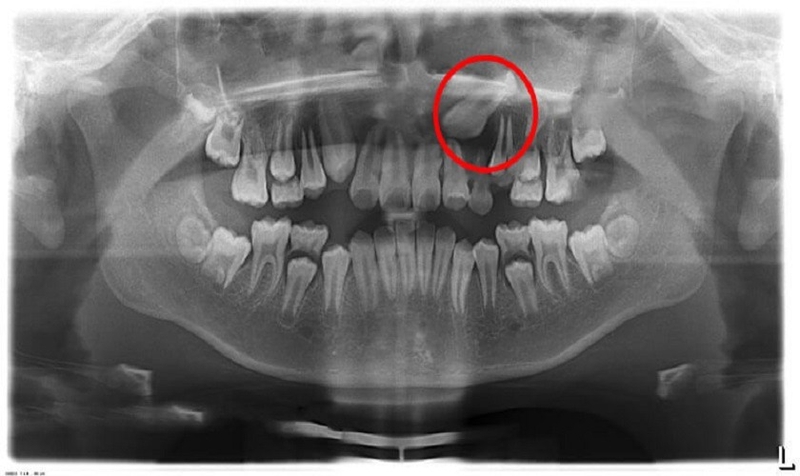

Răng mọc trên lợi là một tình trạng răng phát triển không đúng vị trí trên cung hàm, dẫn đến một loạt các vấn đề nghiêm trọng. Không giống như các tình trạng răng lệch khác, răng mọc trên lợi có thể gây ra sai lệch cơ hàm, mất khả năng nhai, và thậm chí cả tổn thương mô mềm bên trong khoang miệng.

Trong một số trường hợp, răng mọc ngược trên lợi có thể dẫn đến tình trạng răng mọc đảo lộn, mọc đâm chỉa thành nhiều hướng khác nhau. Không chỉ gây mất thẩm mỹ, tình trạng này còn ảnh hưởng lớn tới chức năng ăn nhai của người bệnh.

Đây là tình trạng răng mọc lệch ra khỏi cung hàm, thường mọc lên cao hơn so với các răng còn lại. Nguyên nhân có thể do răng sữa chưa rụng nhưng răng vĩnh viễn đã mọc hoặc do răng có kích thước quá lớn không đủ chỗ để mọc, dẫn đến việc mọc ngược lên phần nướu.

Đây là tình trạng hiếm gặp trong nha khoa, chỉ có vài trường hợp trên thế giới. Nguyên nhân là do mầm răng bị di chuyển quá mức gây ra các vấn đề về hô hấp, viêm xoang.